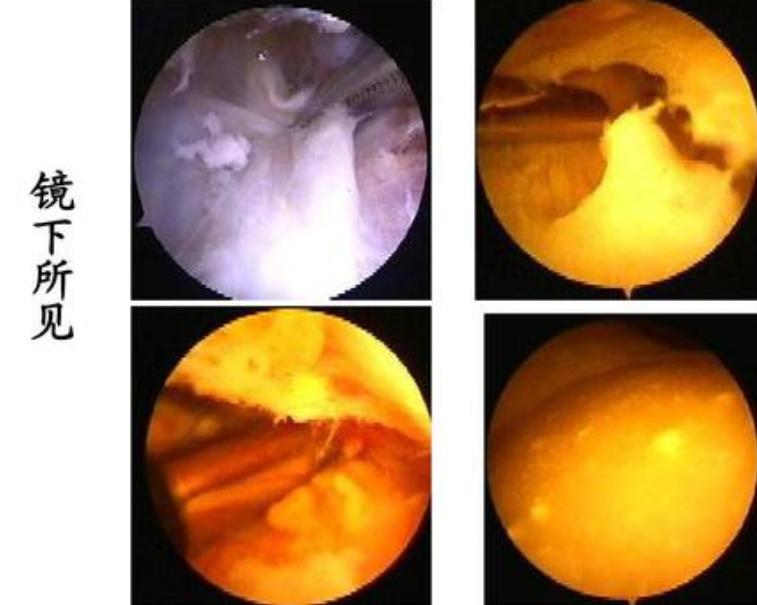

此症状来看,考虑是患了腘窝囊肿。腘窝囊肿就是指腘窝深部滑囊肿大或膝关节滑膜囊向后膨出的统称,引起膝后部疼痛和发胀膝关节伸屈受限,并可触及有弹性的软组织肿块。

最常见的腘窝囊肿系膨胀的腓肠肌、半膜肌肌腱滑囊,该滑囊经常与后关节囊相通,表现为膝关节无力、软弱、关节后部疼痛等。囊肿较大时可妨碍膝关节的伸屈活动,甚至可影响腘窝的静脉回流,出现局部或膝关节以下部位水肿。导致机械性伸膝和屈膝受限,疼痛较轻,紧张膨胀感明显。大部分患者表现为腿疼,坐几分钟再站起就不会走路或好长时间慢慢活动膝关节才行走等。